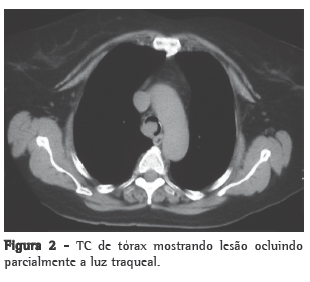

Optou-se por investigar a presença de condições associadas que pudessem estar causando a piora do quadro. A TC de tórax mostrou uma lesão vegetativa da traqueia, localizada a 1,0 cm da carina, com estreitamento endoluminal significativo (Figura 2). A fibrobroncoscopia evidenciou uma lesão endobrônquica violácea, com bordas bem definidas e superfície lisa, implantada na parede lateral direita da traqueia e obstruindo 90% da luz. Não foi realizada biópsia.